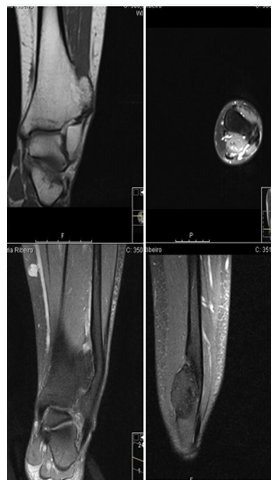

In addition to the X-ray of the left ankle, it was performed Computed tomography (CT) and preoperative Magnetic resonance imaging (MR) for a better definition of the lesion (Figures 2-3).

Figure 3 Preoperative MR, showing the lesion and fibula invasion.